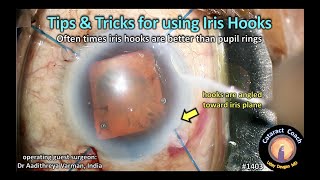

resident cataract surgery case using iris hooks for a small pupil CataractCoach 1403: tips and tricks for using iris hooks

CataractCoach 1403: tips and tricks for using iris hooks Iris hooks. Smal pupil cataract surgery. Resident instruction.

resident cataract surgery case using iris hooks for a small pupil CataractCoach 1403: tips and tricks for using iris hooks

CataractCoach 1403: tips and tricks for using iris hooks Iris hooks. Smal pupil cataract surgery. Resident instruction.